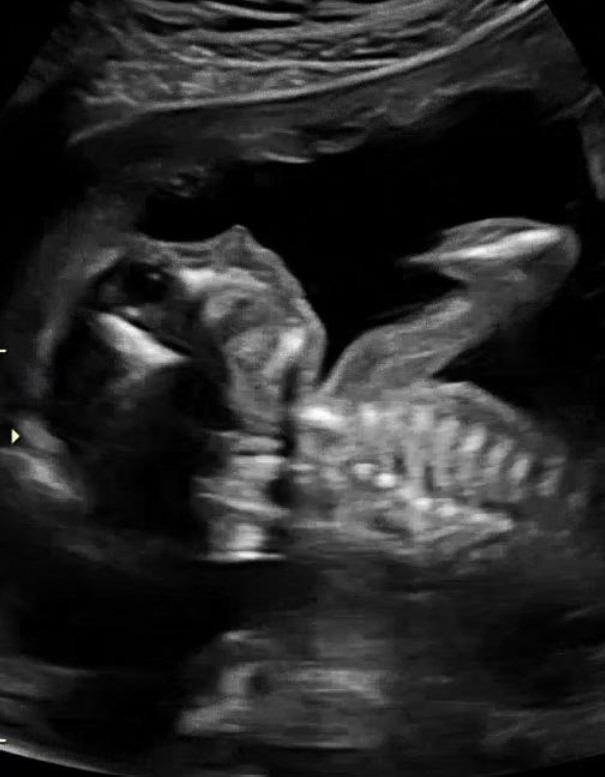

몇 달 전, 소중한 새 생명이 찾아왔습니다! 작년 한 번에 유산의 아픔을 겪은 후 다시 찾아온 너무나 소중한 생명이기에 저와 아내는 하루하루 행복하고 감사한 마음으로 내년에 만나게 될 아기천사 차차를 기다리고 있습니다. 태명이 차차고요.

현재 임신 5개월 차로 차차는 아내 뱃속에서 하루하루 정말 건강하게 잘 자라고 있습니다.